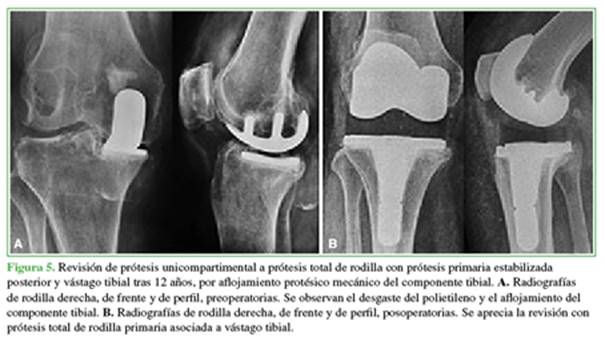

La tasa de complicaciones fue del 6,9% (n = 6), todas fueron menores: una movilización bajo anestesia bilateral en un mismo paciente a las seis semanas de la cirugía inicial, con recuperación completa de la movilidad; dos dermatitis de la herida, una dehiscencia y una necrosis superficial, todas con buena evolución mediante tratamiento ambulatorio. Tres rodillas en tres pacientes (3,5%) evolucionaron a aflojamiento mecánico aséptico, uno de ellos traumático, por lo que se procedió a la revisión y conversión a PTR en dos casos, y la revisión del componente tibial unicompartimental a nuevo platillo tibial PUC all poly en el restante, tras 12, 8.6 y 7 años, respectivamente. La supervivencia de la prótesis fue del 96,5% a los 6.1 años (rango 1.1-17) (Figuras 5 y 6).

Dos pacientes requirieron revisión a PTR y uno, a revisión del componente tibial PUC por nuevo platillo tibial PUC all poly por aflojamiento aséptico, tras 12, 8.6 y 7 años, respectivamente. Según la bibliografía y nuestra experiencia, en la mayoría de los casos de conversión a PTR, esta puede realizarse de forma relativamente sencilla, y es necesario el uso de vástagos e implantes de revisión solo en un tercio de los casos.24 Si las restantes estructuras articulares están indemnes, existe evidencia de buenos resultados tras la revisión a nueva PUC.19,25 De forma similar, Romagnoli y cols. publicaron la mayor cohorte hasta la fecha con 220 PUC bilaterales, y comunicaron tasas de revisión del 3,5% para las PUC bilaterales en un tiempo, sin diferencias respecto al grupo de PUC unilateral.8 La supervivencia de la prótesis fue del 96,5% tras 6.1 años de seguimiento.